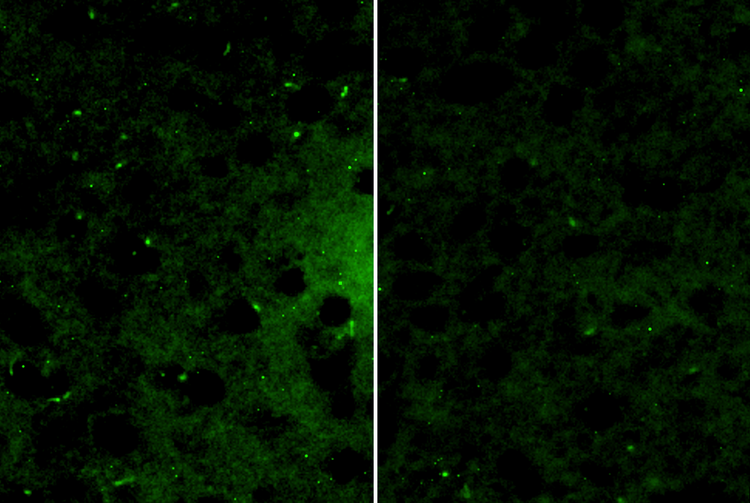

Professor Kobayashi: Mice were subjected to short-term (3 days) and long-term (21 days) restraint stress, and the primary cilia in the prefrontal association area (FrA)3 of the brains of these mice were observed and analyzed (Figure 1). Under short-term stress, temporary shortening of cilia and a decrease in ciliated cells were observed.

However, both normalized after the mice were freed from stress, and no behavioral abnormalities were observed. On the other hand, when the mice were exposed to long-term stress, the shortening of cilia and the decrease in cilia-bearing cells persisted even after the stress was relieved, and pronounced depressive behavior was observed. Therefore, the loss of the ability to recover from ciliary changes may trigger the onset of depressive behavior.

Figure 1. Comparative images of primary cilia in the brains of control mice and mice subjected to 21 days of stress. Marked shortening of the primary cilia and a significant decrease in ciliated cells were observed in the stress group (Figure 1b, right image). Green indicates neuronal primary cilia stained with the cilia marker (AC3).

Left: a) Control group mice. Imaging conditions: vessel: glass slide; objective lens: LUCPLFLN20XPH.

Right: b) Mice in the stress group (restrained for 21 days). Imaging conditions: vessel: glass slide; objective lens: LUCPLFLN20XPH.

Images courtesy of Professor Yuki Kobayashi, Hiroshima University.

First, the superior autofocus performance is a notable advantage. Cilia are elongated structures less than 10 μm in length, and even slight shifts in focus can reduce measurement accuracy. Using the APX100 enabled us to achieve stable focusing at multiple points, facilitating accurate observation and measurement of ciliary dynamics during stressful states, as shown in Figure 1.